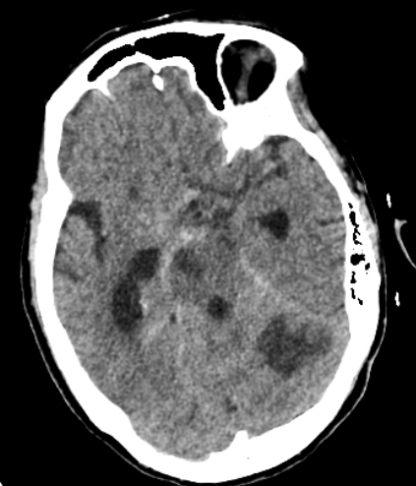

| 蛛网膜下腔出血并脑室系统扩张;脑干、左侧小脑半球见斑片状低密度灶;右侧眶尖部见片状软组织密度影 图 3 患者入院第3天头颅CT |

患者,72岁女性,因“头痛伴反应差1 d,呕吐1次”入本院神经外科。患者入院前1 d突发头痛,伴意识状态差,不能行走,伴呕吐1次,呕吐物为胃内容物,无抽搐、发热。入院时体温36.5℃,血压187/97 mmHg(1 mmHg=0.133 kPa),神志嗜睡,表情淡漠,GCS评分12分,双侧瞳孔不等大,左侧直径2.5 mm,直接对光反射灵敏,间接对光反射消失,右侧直径4.0 mm,直接和间接对光反射均消失,双侧巴氏征阴性。既往曾出现右侧眼睑下垂,右眼视力变差,1个月前右眼视力丧失,曾在外院诊断为右侧视神经炎性假瘤,有高血压病史,否认手术史及免疫缺陷病史。入院头颅CT提示右侧视神经孔占位性病灶,视神经脑膜瘤可能(图 1)。头颅MR提示:①右侧基底节区、中脑、脑桥、双侧小脑半球多发斑点状/斑片状新鲜脑梗塞灶;②双侧基底节区、放射冠多发斑点状/斑片状脑梗塞灶或缺血变性灶;③右侧眶尖条片状异常信号灶,性质待定(图 2)。经神经内科会诊后考虑急性脑梗死,转入神经内科治疗,神经内科治疗上给予抗血小板、甘露醇脱水降颅内压、营养神经对症处理。患者入院后反复出现发热,发热原因未明,入院第2天经家属同意后行腰椎穿刺留取脑脊液行高通量基因测序。入院第3天,患者病情加重,神志转昏迷,复查头颅提示:①鞍上池、环池、天幕缘见片状稍高密度,考虑蛛网膜下腔出血。脑干、左侧小脑半球见斑片状低密度灶,范围大致如前,考虑脑梗塞,脑干片状低密度灶密度更低,请结合临床;②脑白质病变,脑萎缩,同前;③右侧眶尖部见片状软组织密度影,大小约16 mm×9 mm,性质待定,同前片,建议MR平扫+增强检查协诊(图 3)。考虑蛛网膜下腔出血合并脑室系统扩张,转神经外科急诊行脑室外引流+全脑血管造影术,脑血管造影未见脑动脉瘤及畸形改变(图 4)。术后转入ICU监护治疗,转入ICU后脱水降颅内压、抗感染、脑保护、预防脑血管痉挛等治疗。患者术后出现双侧瞳孔散大,复查头颅提示蛛网膜下腔出血较前增多,双脑室积血、积气,脑干、左侧小脑半球见斑片状低密度灶。入院第4天,脑脊液高通量基因检测结果报告为烟曲霉感染,脑脊液及血液半乳甘露聚糖检测(GM试验,金域)结果分别为6.19/1.42,阳性。综合病史、CT及MR结果,临床诊断为脑烟曲霉感染,改用伏立康唑注射液积极抗真菌治疗,白蛋白联合激素脱水减轻脑水肿、尼莫地平抗脑血管痉挛及脑保护等综合措施。患者体温热峰下降,但持续深昏迷,神经反应差,入院第7天家属放弃治疗出院。

脑曲霉菌感染合并蛛网膜下腔出血较为少见,文献报道多为个案[8]。本例患者肺部及鼻窦部菌未发现曲霉菌感染临床表现以及影像学表现,但头颅CT可见右侧蝶窦外侧骨质缺失,临近眶尖见软组织团块,软组织团块与视神经、眼肌分界不清。MRI见右侧眶尖见软组织团块,T1WI呈等/高信号,T2WI呈等/高信号,DWI呈等/高信号,ADC呈等/高信号,行脑血管造影时未见眼眶有造影剂聚集,结合患者入院2月前在外院发现右侧视神经孔占位性病变并行激素冲击治疗,因而,临床高度考虑患者右侧视神经孔曲霉菌感染,经激素冲击治疗后此位置的直接蔓延导致颅内曲霉菌感染。遗憾的是,入院后患者病情变化迅速,未能获取右侧视神经孔活检进一步明确诊断。尽管在入院第4天明确脑曲霉菌感染,并给予伏立康唑注射液积极抗真菌治疗,但患者病情进展迅猛未能获得良好预后。本例患者急性多发脑梗死及蛛网膜下腔出血考虑与烟曲霉侵犯嗜血管性有关,颅内组织缺血缺氧性坏死,造成脑血管意外的发生,而曲霉菌引起的变态反应加重或导致了恶性脑水肿,最终造成患者不良预后。